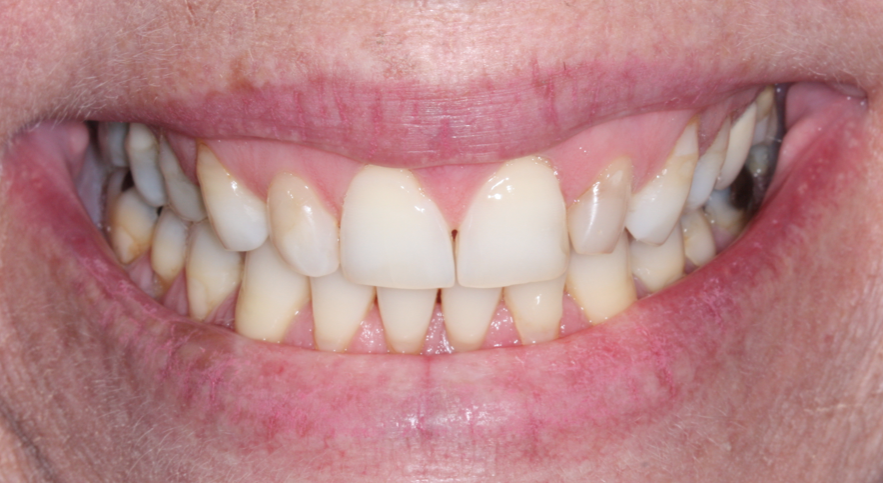

Paciente L.M., 53 anos, apresentava sensibilidade durante a mastigação e relatava mau hálito na região do dente 25. Durante análise clínica, a paciente apresentava sorriso alto (Figura 1). Após análise tomográfica, foi constatada uma perfuração radicular no dente em questão e que a raiz estava em contato com a tábua vestibular, sendo que esta possuía ≥1mm de espessura em seu terço cervical (Figura 2). Após a paciente concordar com o plano de tratamento, foi realizado a instalação imediata de um implante Cone Morse de corpo cônico (Due Cone 3.5×11, Implacil De Bortoli, São Paulo, Brasil), regeneração óssea guiada com osso bovino inorgânico e colocação de uma barreira regenerativa de politetrafluoretileno denso.